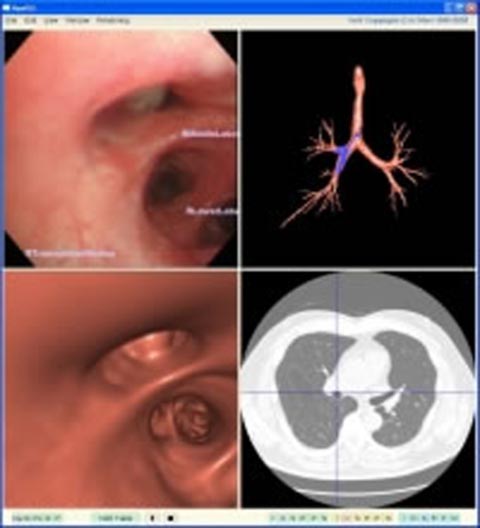

●軟性内視鏡検査ナビゲーション

気管支や大腸などの検査では、自由に曲げることのできる軟性内視鏡が用いられます。腹腔鏡手術では、本体が固い筒状の硬性内視鏡が使われており、手元側に位置センサを装着すれば、内視鏡先端位置の推定することができます。しかしながら、軟性内視鏡ではこの手法が使えず、内視鏡画像音仮想化内視鏡画像を比較することによって内視鏡先端位置を推定する手法、超小型磁気式位置センサを利用して内視鏡先端位置を推定する手法などが開発されています。この手法を利用することによって、現在の内視鏡位置を医師につたえ、検査すべき個所に誘導する内視鏡検査ナビゲーションの研究を行っています。

図6 気管支鏡検査ナビゲーションシステムの例